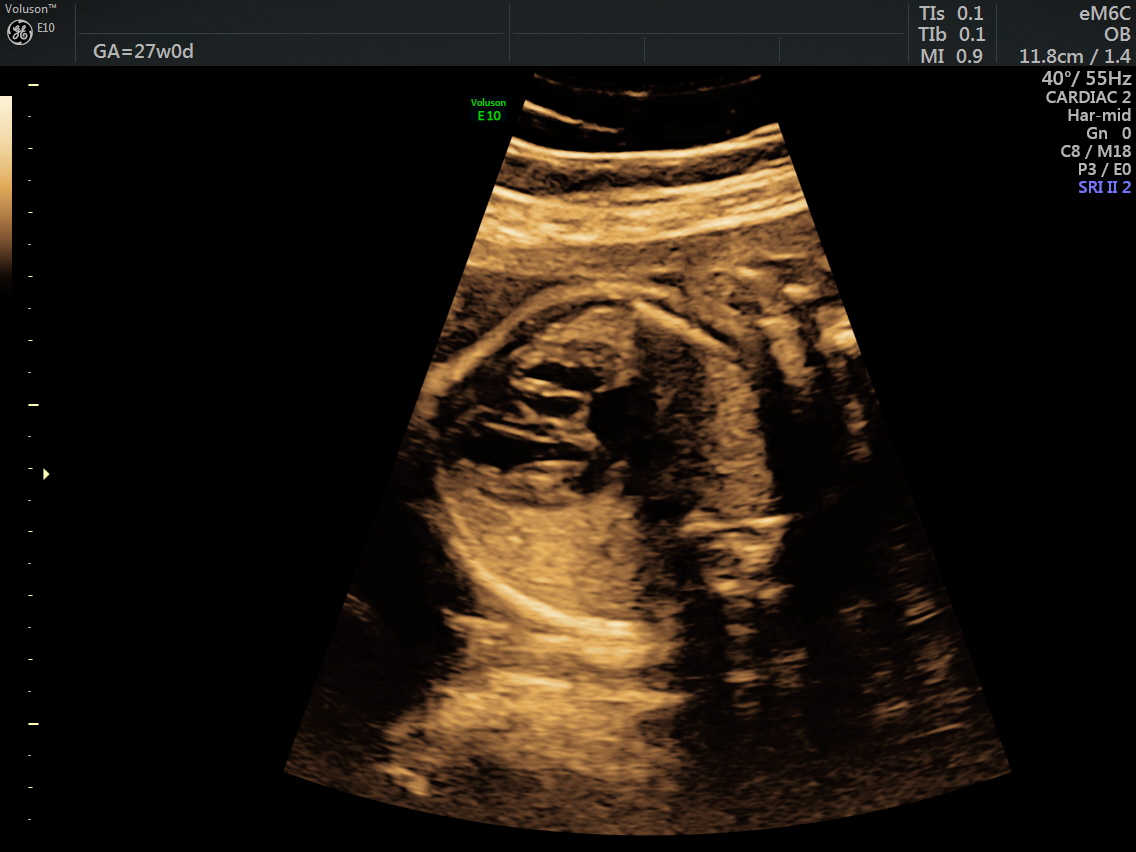

RT AORTIC ARCH_13 Published June 17, 2016 at 1136 × 852 in Rt aortic arch and aberrant left subclavian artery ← Previous Next →